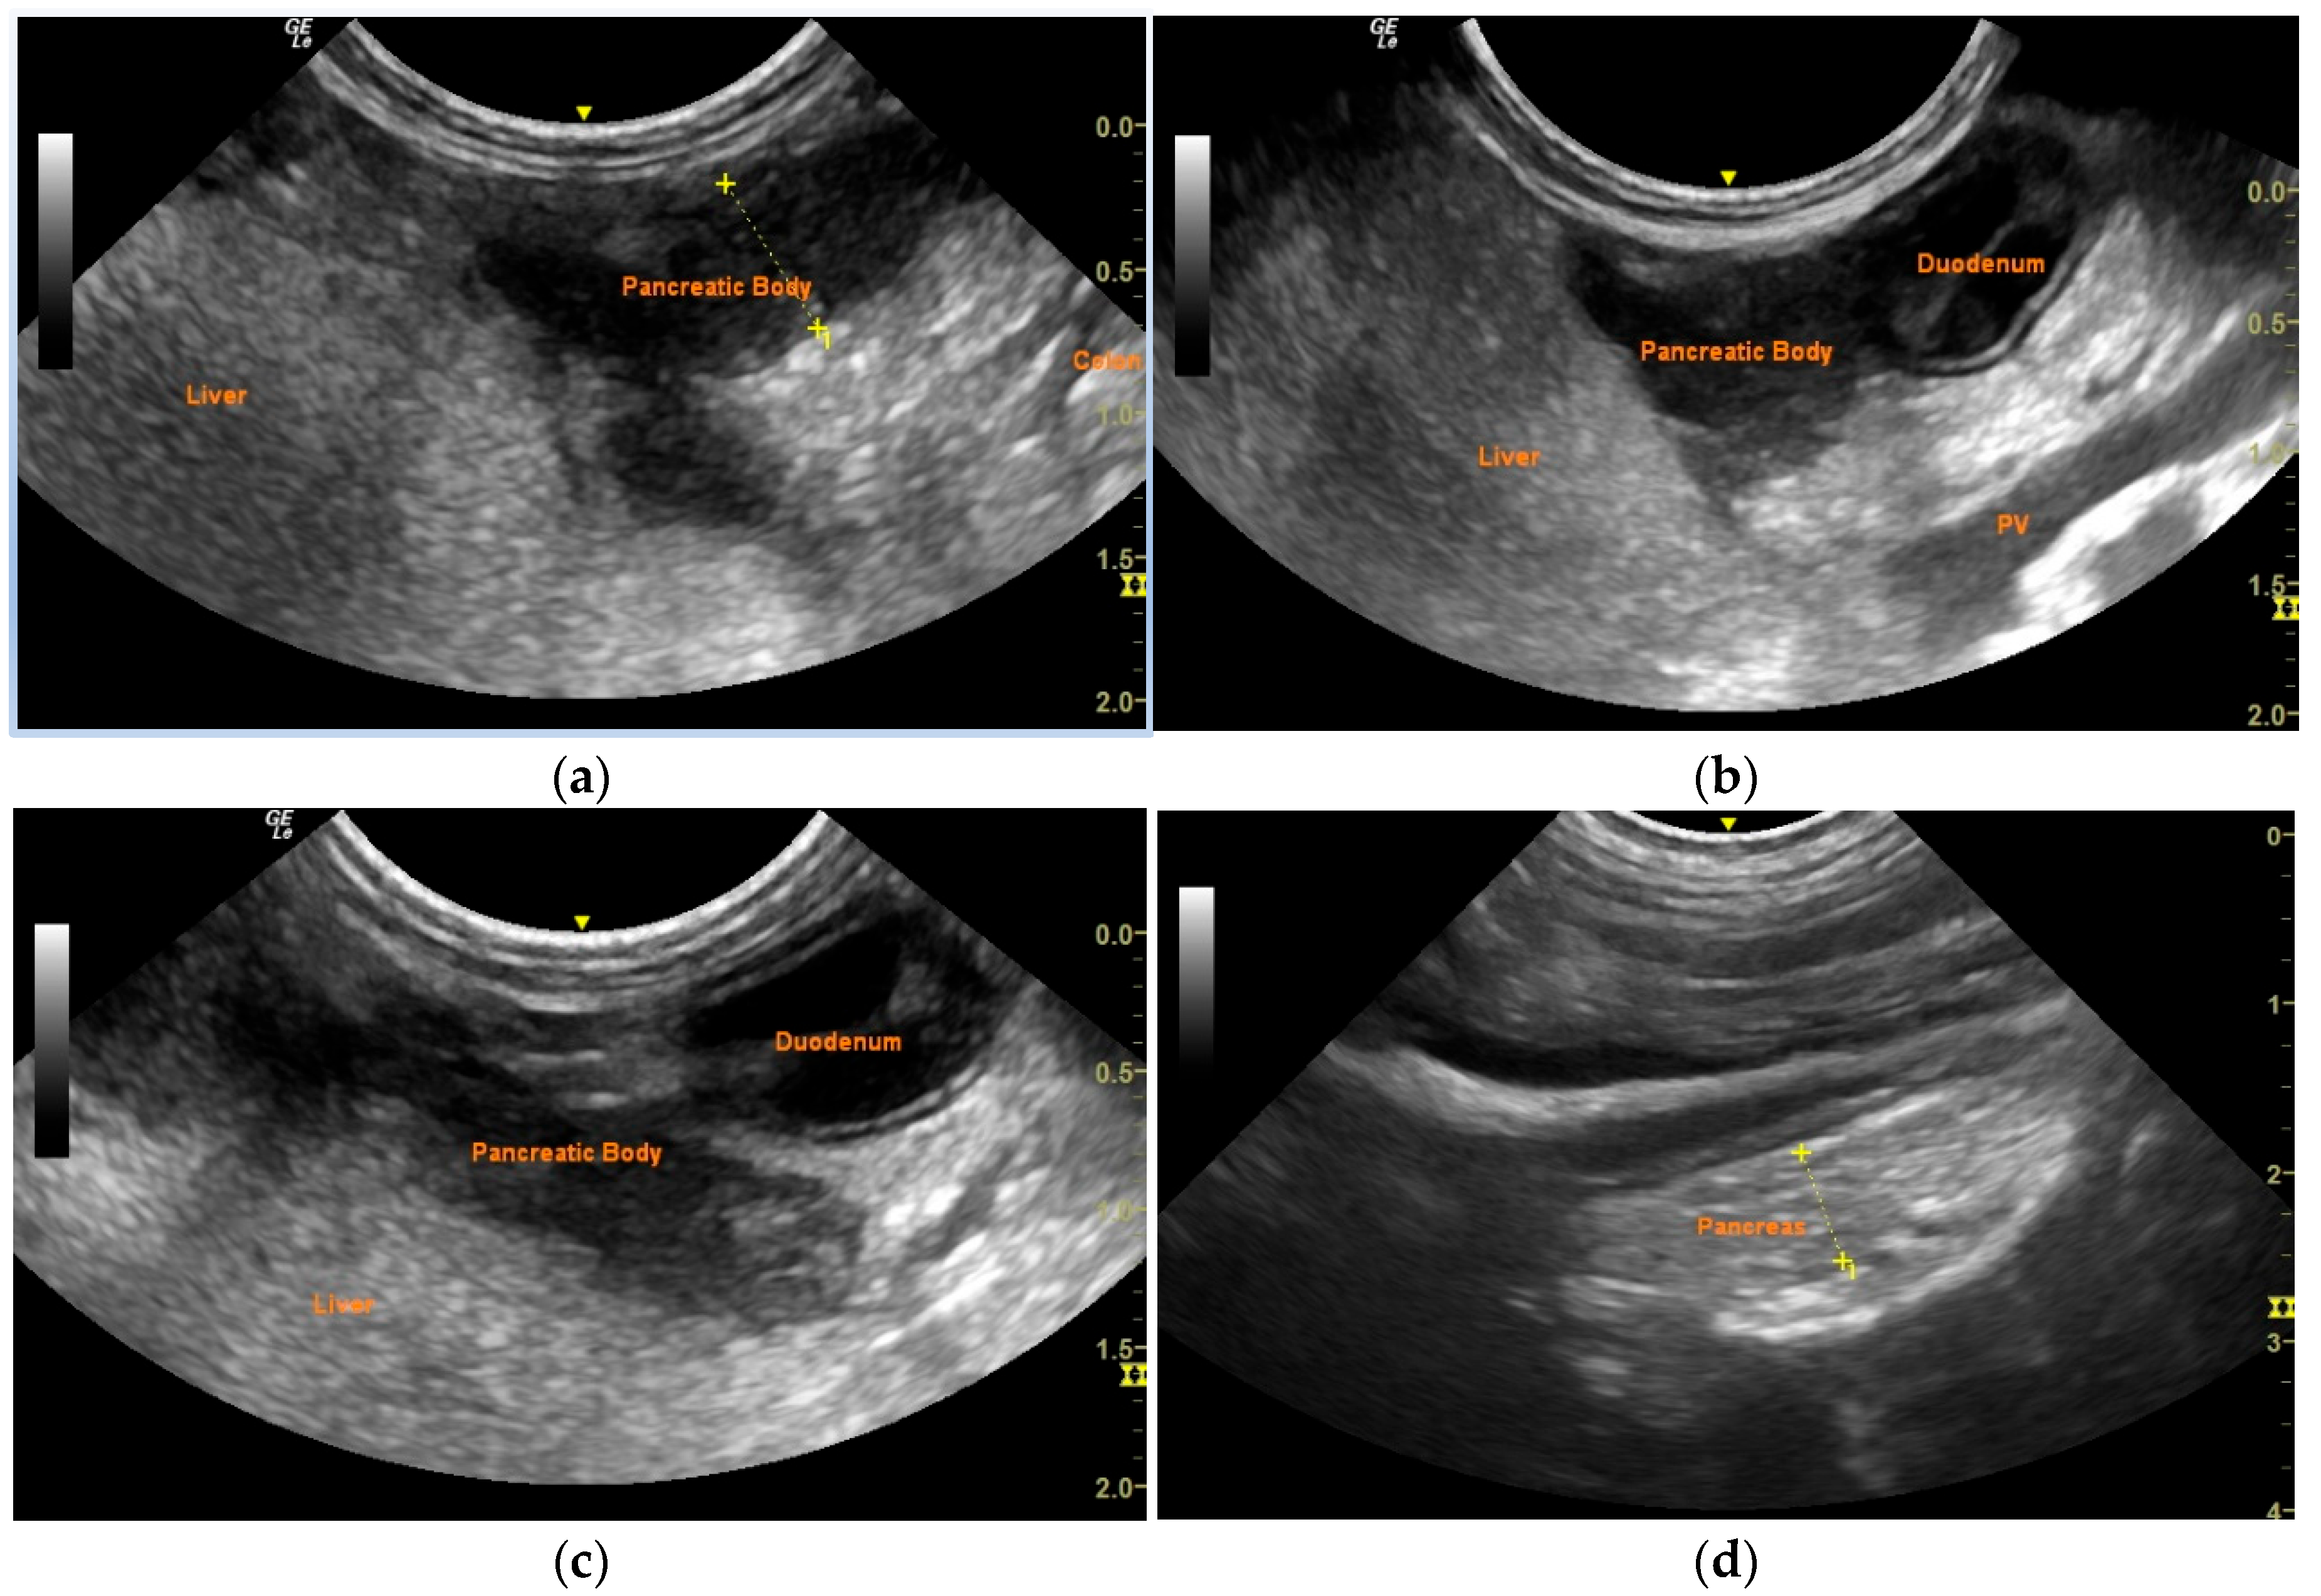

2. Case Description